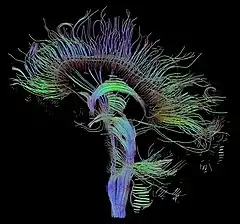

Selected image –

T1-weighted MRI scans (with contrast) of the same brain slice at monthly intervals. Bright spots indicate active lesions of multiple sclerosis.

Photo credit: Public domain (U.S. Brookhaven National Laboratory)